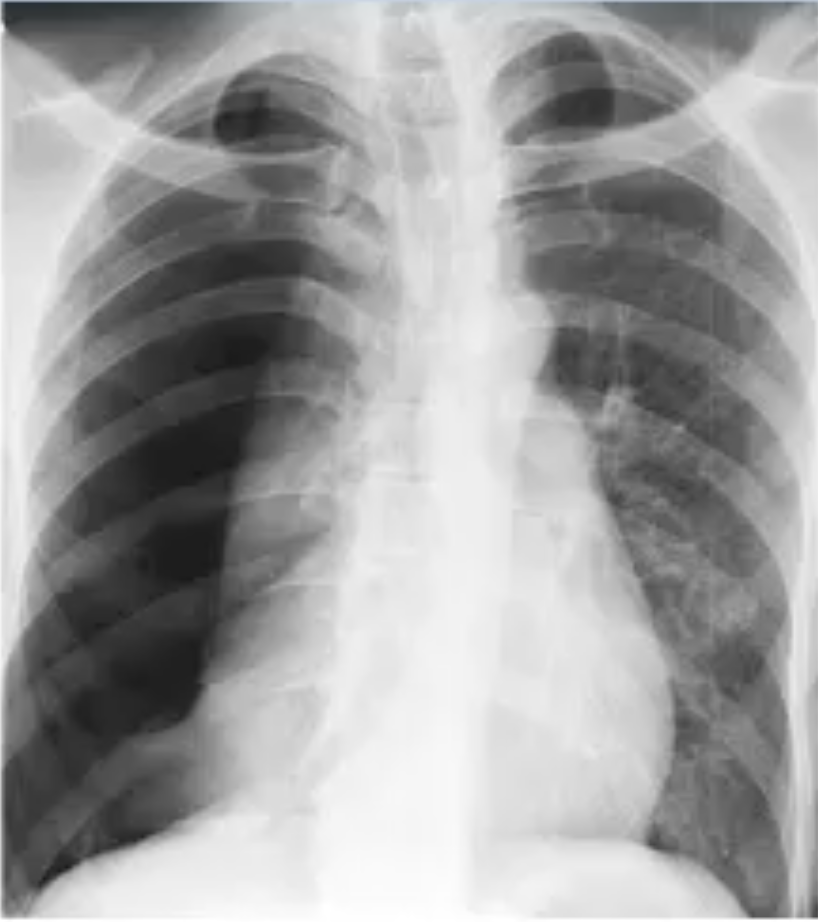

Which diagnosis is suggested by this CXR?

Pneumothorax

No lung markings on affected side

Mediastinum deviated away from the lesion